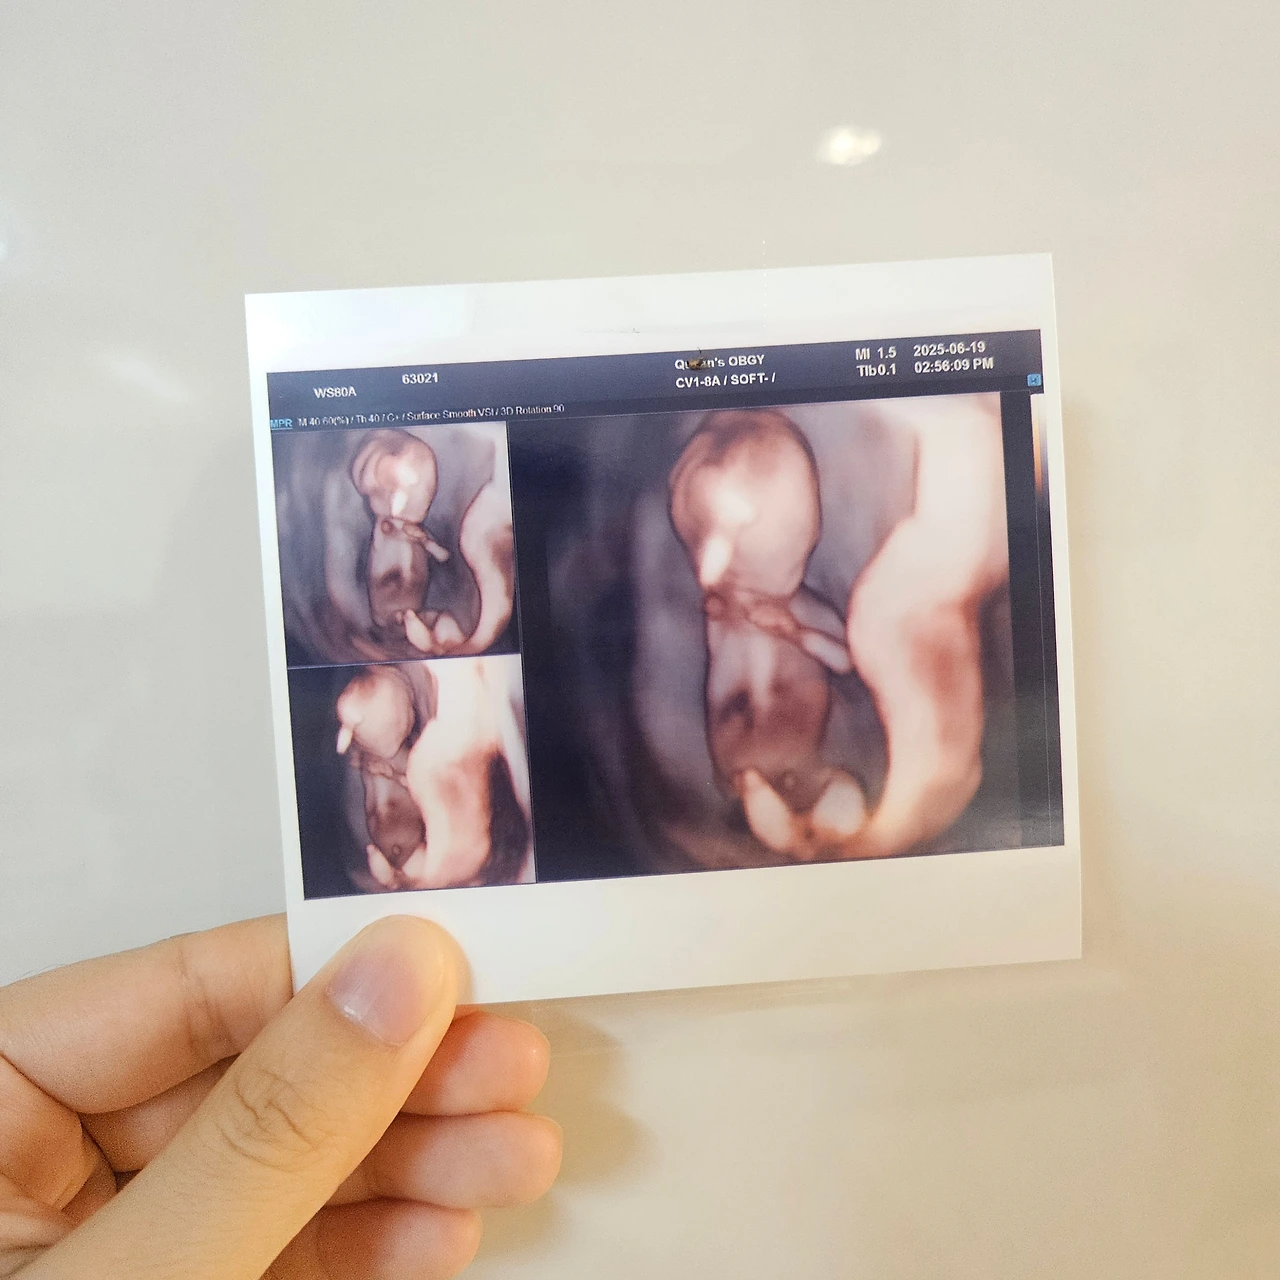

언젠가 이런 글을 쓰게 될 날을 고대했던 것 같습니다. 뜸 들이지 않고 발표할게요. 배속에 소중한 생명이 자라고 있어요! 이 글이 발행될 때는 아마도 18주 차를 지나고 있겠네요. 출산까지 완전한 안정기는 없다지만 1, 2차 기형아 검사도 모두 통과했고, 꼬물꼬물 태동도 느낄 수 있을 정도가 되었으니 이제는 소식을 전해도 괜찮다는 마음이 듭니다.

걱정되는 마음에 일이 손에 잡히지 않았고 정신은 딴 데 빼둔 채로 몸만 한의원에 앉아있는 날들이 늘어갔지만, 제 마음이 우습기라도 하다는 듯 기쁨이는 무럭무럭 주수에 맞게 자라주었어요. 병원에 갈 때마다 점점 사람의 형태가 되어가는 기쁨이의 모습을 보며 아기가 오히려 "걱정 좀 그만하시라고요!" 라고 응원을 건네주는 것만 같았습니다.

이제는 뇌도 예쁘게 생겼고, 척추 뼈도 올곧고, 갈비뼈들도 촘촘히 보인답니다. 손가락, 발가락은 물론이고 팔다리도 점점 길쭉해지고 있어요. 벌써부터 몸도 너무 무겁고, 소화도 안되고, 잠도 푹 잘 수가 없어서 힘들고 지쳤었는데, 이렇게 임신 초기부터 다시 떠올려보니 감회가 새롭고 새삼스레 감사한 마음이 듭니다. 문우분들께도 소식을 전할 수 있게 되어 진심으로 기쁘고 행복해요. 그간 제가 힘들 때 함께 걱정하고 위로해 주셔서 정말 큰 힘이 됐어요. 어떤 말로도 부족할 만큼 감사하고 또 감사합니다.

13주차 기쁨이 첫 입체초음파